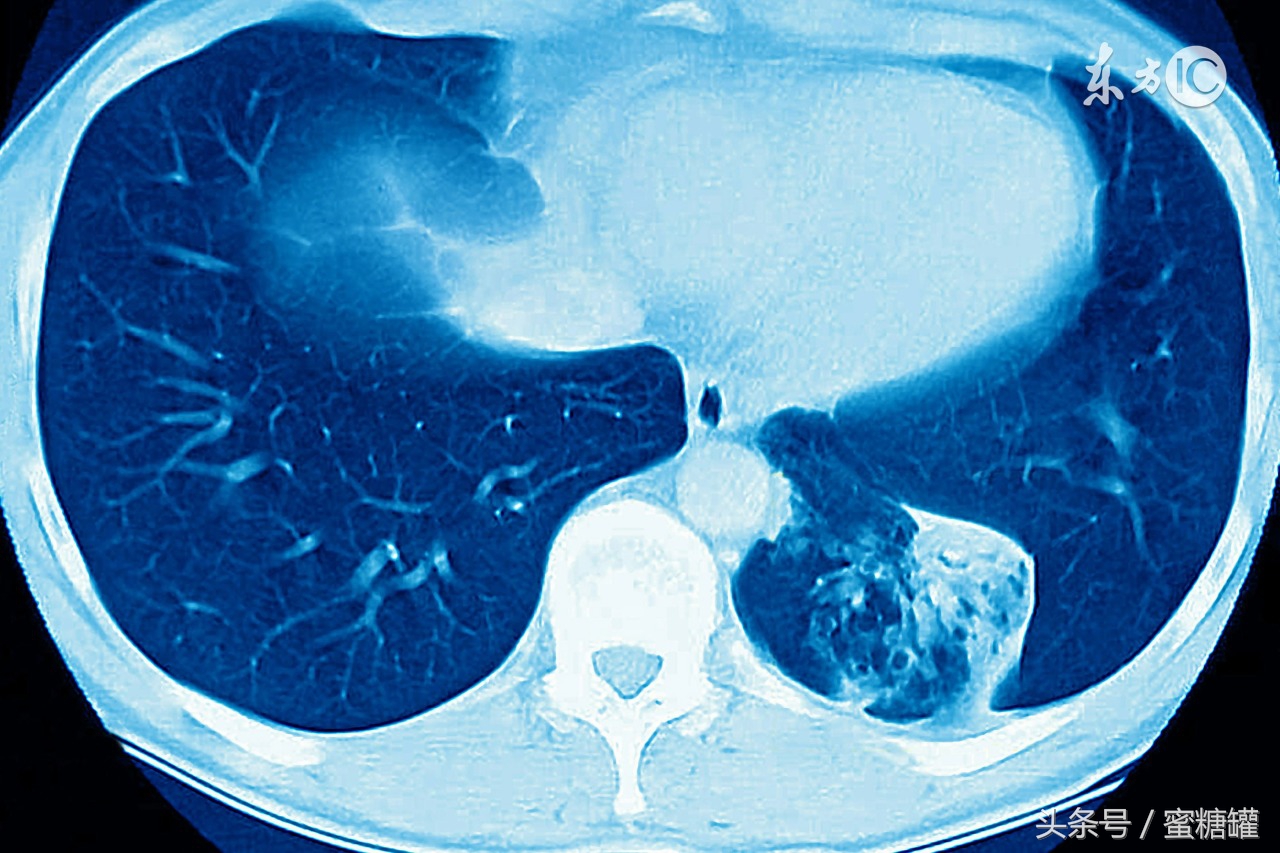

肺癌

咳嗽不止

痰中带血丝

气短

出现喘鸣音

反复发作的肺炎或支气管炎

声音嘶哑

胸痛,尤其是在深呼吸、咳嗽或大笑的时候胸痛程度加重